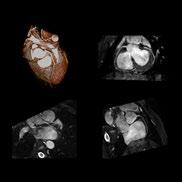

Cardiac screening for proactive health surveillance is firmly on the radar for all sporting organisations. This is not only to identify undetected anomalies that could put life and health at risk, but also to monitor for the onset of coronary artery disease as players age. Indeed, from youth teams to the veteran professional footballer, anyone undertaking vigorous training and competitive matches is regulated to receive cardiology profiling every 2 years1

The imaging tool that has traditionally been used is ultrasound echocardiography, looking at the structure of the heart at rest and during stress exercise. Now, and increasingly, the structure and functionality of the heart is examined via the latest generation in MRI.

For example, new developments have accelerated the examination time for cardiac MRI, with fewer patient breath holds needed to deliver much more detailed, richer image outputs that give another level of screening and profiling of the more subtle presentations of cardiac anatomy.